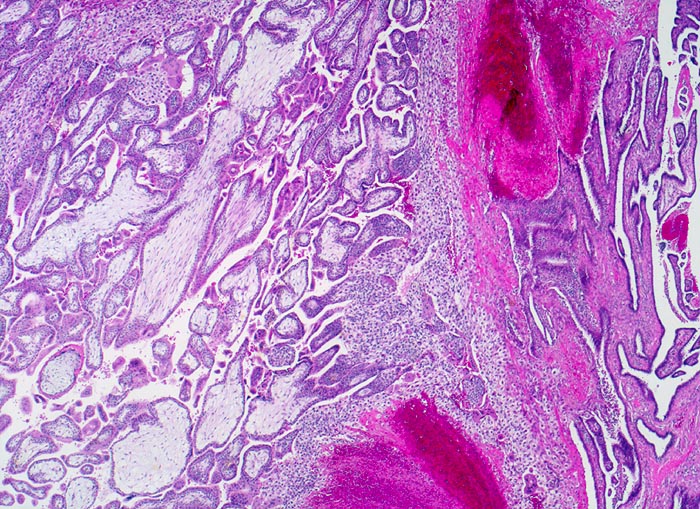

PathoPic ID 3871 - Tubargravidität

Tubargravidität

Tuba uterina

Rechts im Bild Tubenschleimhaut. Links im Bild Dezidua und Plazentarzotten aus Frühschwangerschaft.

Extrauteringravidität